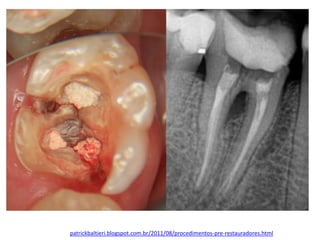

• Os dentes submetidos a tratamento endodôntido

precisam ter a câmara pulpar hermeticamente

vedada tanto entre as sessões quanto após o

término do procedimento. (PINHEIRO et al.,

1997; PECORA, 2002).

patrickbaltieri.blogspot.com.br/2011/08/procedimentos-pre-restauradores.html